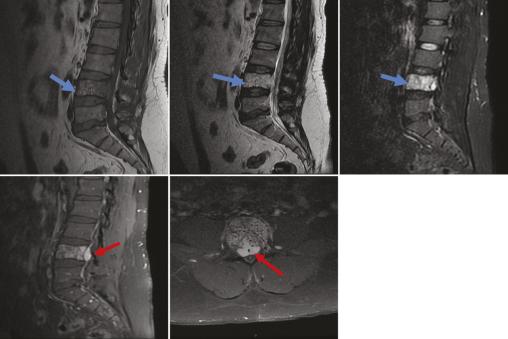

Un homme âgé de 42 ans, sans antécédents notables, souffre depuis un an de lombosciatalgies bilatérales d’aggravation progressive, avec installation, depuis trois jours, de troubles génitosphinctériens à type de rétention urinaire évoluant dans un contexte d’apyrexie et de conservation de l’état général. À l’examen clinique, le patient est conscient, stable sur le plan hémodynamique et respiratoire. L’examen neurologique objective une parésie des deux membres inférieurs avec des réflexes ostéotendineux vifs. Une imagerie par résonance magnétique (IRM) médullaire, réalisée en urgence, met en évidence une lésion de la quatrième vertèbre lombaire en hypersignal T1 et STIR, de signal hétérogène en T2, se rehaussant après injection du produit de contraste avec une épidurite antérieure en regard, responsable d’une compression du fourreau dural (fig. 1). Un complément scanographique sans injection de produit de contraste, réalisé par la suite, objective la lésion ostéolytique du corps vertébral de L4, avec un aspect piqueté épais d’os dense (en têtes d’épingle) sur la coupe axiale et grillagé sur la reconstruction sagittale, faisant évoquer un hémangiome osseux agressif (fig. 2). Le patient a bénéficié en urgence d’une laminectomie lombaire en regard de L4, avec une bonne amélioration clinique.

Les hémangiomes vertébraux sont des tumeurs bénignes le plus souvent asymptomatiques. Ils sont rarement agressifs (moins de 1 % des cas),1 touchent l’adulte entre 40 et 60 ans, avec une prédominance féminine.1 La localisation dorsale est la plus fréquente, suivie par l’atteinte lombaire.2 Le tableau clinique est celui d’une compression médullaire et/ou radiculaire secondaire à une extension progressive de l’hémangiome dans le canal vertébral.1 La radiographie standard, souvent réalisée en première intention, montre une lésion osseuse lytique renfermant des trabécules verticales (signe en velours côtelé). L’imagerie en coupe (tomodensitométrie [TDM] et IRM) occupe une place primordiale dans le diagnostic positif. Le scanner objective l’hémangiome osseux sous forme d’une lésion osseuse mixte sclérotique renfermant de la graisse avec visualisation des trabéculations verticales réalisant un aspect piqueté épais d’os dense (en têtes d’épingle) sur la coupe axiale et grillagé sur la reconstruction sagittale.3 À l’IRM, l’aspect des hémangiomes varie en T1 en fonction de la quantité de graisse, la perte de l’hypersignal T1 est un des critères d’agressivité de l’angiome, ils sont visibles en hypersignal T2, et le rehaussement est souvent présent. L’IRM permet également de mettre en évidence une épidurite et la compression médullaire ou radiculaire.3 Les caractères d’agressivité de l’hémangiome sont une localisation entre la 3e et la 10e vertèbre dorsale, l’atteinte de l’ensemble du corps vertébral, l’extension à l’arc postérieur, l’aspect discontinu des corticales, l’extension dans les parties molles paravertébrales ou intracanalaires à l’IRM. En cas de doute diag­nostique, l’examen anatomopathologique reste la référence. La prise en charge repose sur un geste de décompression en ­urgence, précédé, si possible, par une embolisation. La vertébro­plastie peut être associée en cas de syndrome vertébral douloureux.